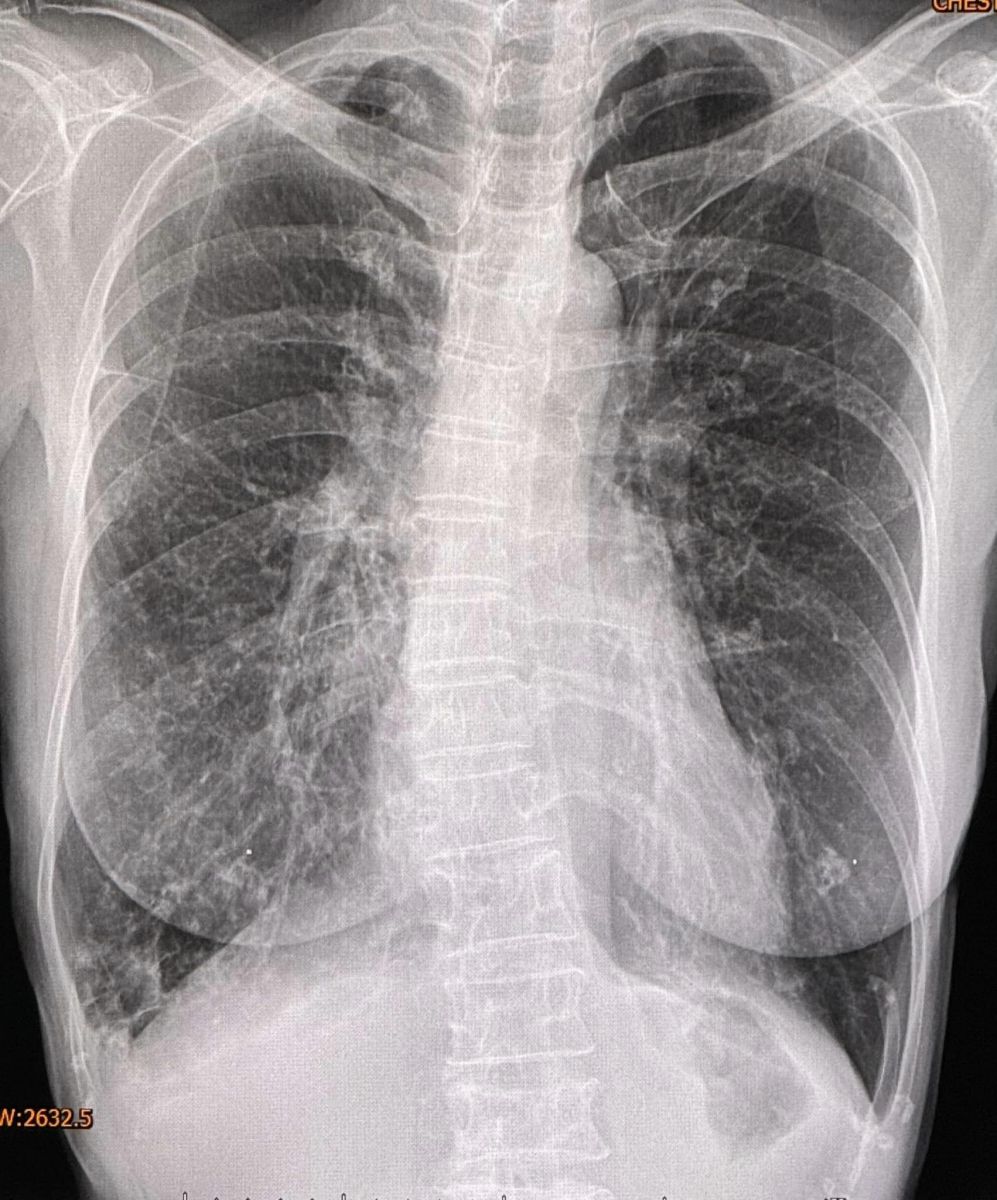

จากการตรวจร่างกาย ฟังปอดมีเสียงผิดปกติทั้ง 2 ข้าง เอกซเรย์ปอดผิดปกติเข้าได้กับหลอดลมโป่งพองทั้ง 2 ข้าง (ดูรูป) ทำคอมพิวเตอร์ปอดเห็นหลอดลมโป่งพองในปอดทั้ง 2 ข้าง (ดูรูป) ส่งเสมหะย้อมเชื้อหาวัณโรค AFB smear ให้ผลบวก วินิจฉัย: โรคหลอดลมโป่งพอง สงสัยติดเชื้อวัณโรค หรือวัณโรคเทียม จึงให้ยา INH,rifampicin,ethambutol รักษาวัณโรค ร่วมกับ azithromycin รักษาวัณโรคเทียม 2 สัปดาห์ หลังกินยาดีขึ้น หยุดไอ ไม่มีเสมหะ ผลเพาะเชื้อขึ้นเชื้อวัณโรคเทียม 3 ชนิด คือ M.fortuitum, M. intracellulare และ M. gordonae เมื่อทราบผลเพาะเชื้อได้หยุดยาทุกชนิดก่อน ขอเก็บเสมหะอีกครั้งแต่เก็บไม่ได้ เพราะไม่มีเสมหะ แนะนำให้หยุดการเทปุ๋ยรอบต้นไม้ในสวน